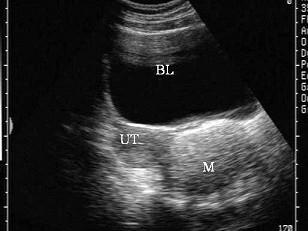

如图,女性,26岁,无明显不适,盆腔横断面,最可能的诊断是?(?)A.炎性包块B.宫外孕C.畸胎瘤D.黄体囊肿E.正常声像图

问题 如图,女性,26岁,无明显不适,盆腔横断面,最可能的诊断是?(?)

选项 A.炎性包块 B.宫外孕 C.畸胎瘤 D.黄体囊肿 E.正常声像图

答案 C